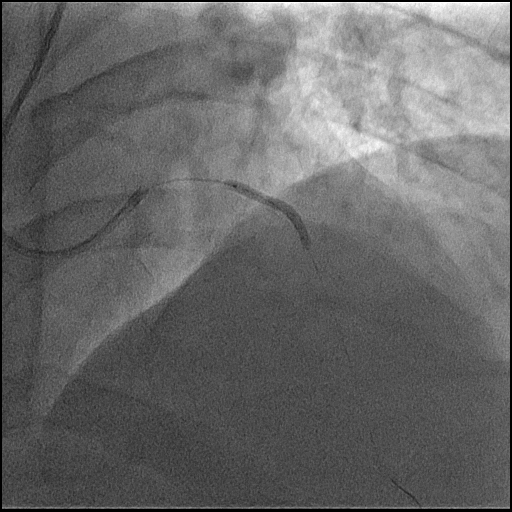

Coronary angiography has been performed, right coronary artery couldn't be find in the right coronary ostium, with EBU 3.5 right coronary artery was visualized arising from the left coronary ostium. LAD was occluded and RCA was with 99% stenosis in mid segment.

Diagnostic angiography has been performed and occluded Left Anterior descending artery was visualized but, the right coronary artery couldn't be find from the right coronary ostium. 6F EBU 3.5 catheter trough the right radial approach has been inserted and we could visualize right coronary artery arising from the left coronary ostia. Direct stenting was performed with 3.5/38mm DES at 17 atm. After this procedure we continued to LAD, passed the occlusion with BMW wire after which predilatation with 2.5/20 mmx 14 atm has been performed and after that 3.0/28mm DES at 15atm was implanted with good end result